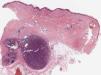

A 78-year-old woman with no remarkable past history presented with nodular lesions of 2 years’ duration on both legs. The lesions were asymptomatic, and while they had not grown, they had increased in number. Physical examination showed multiple nodules measuring less than 2cm covered by normal-appearing skin on both legs and a few nodules on the thighs. The nodules were soft on palpation and not fixed to the deep layers (Fig. 1). There was no associated edema or mucosal involvement. The general blood test results were normal and serology for hepatitis C virus (HCV), HBV, and human immunodeficiency virus (HIV) was negative. Ultrasound showed numerous solid subcutaneous lesions in both legs. The findings were heterogeneous, with a mixture of hyperechogenic and strongly hypoechogenic lesions without detectable flow. Histologic examination showed a well-circumscribed nodule composed of spindle cells with varying degrees of atypia (Fig. 2) in the subcutaneous tissue, in addition to large irregular, dilated vascular channels with a prominent endothelium and abundant hematic content (Fig. 3). Immunohistochemistry was positive for CD31 and HHV-8. Positron emission tomography–computed tomography (PET-CT) ruled out lymph node and visceral involvement and confirmed exclusive involvement of the subcutaneous tissue. A diagnosis of primary KS of the subcutaneous tissue was established. Considering the absence of disease spread and severe symptoms, it was decided to adopt a watch-and-wait approach.

A and B, Higher-magnification histologic images showing that the nodule is formed by spindle cells with varying degrees of atypia intermingled with dilated, irregular vascular channels (hematoxylin-eosin, original magnification ×10). C, Spindle cells showing positive staining for human herpes virus 8 (monoclonal antibody, ORF73/HHV-8; original magnification ×20).